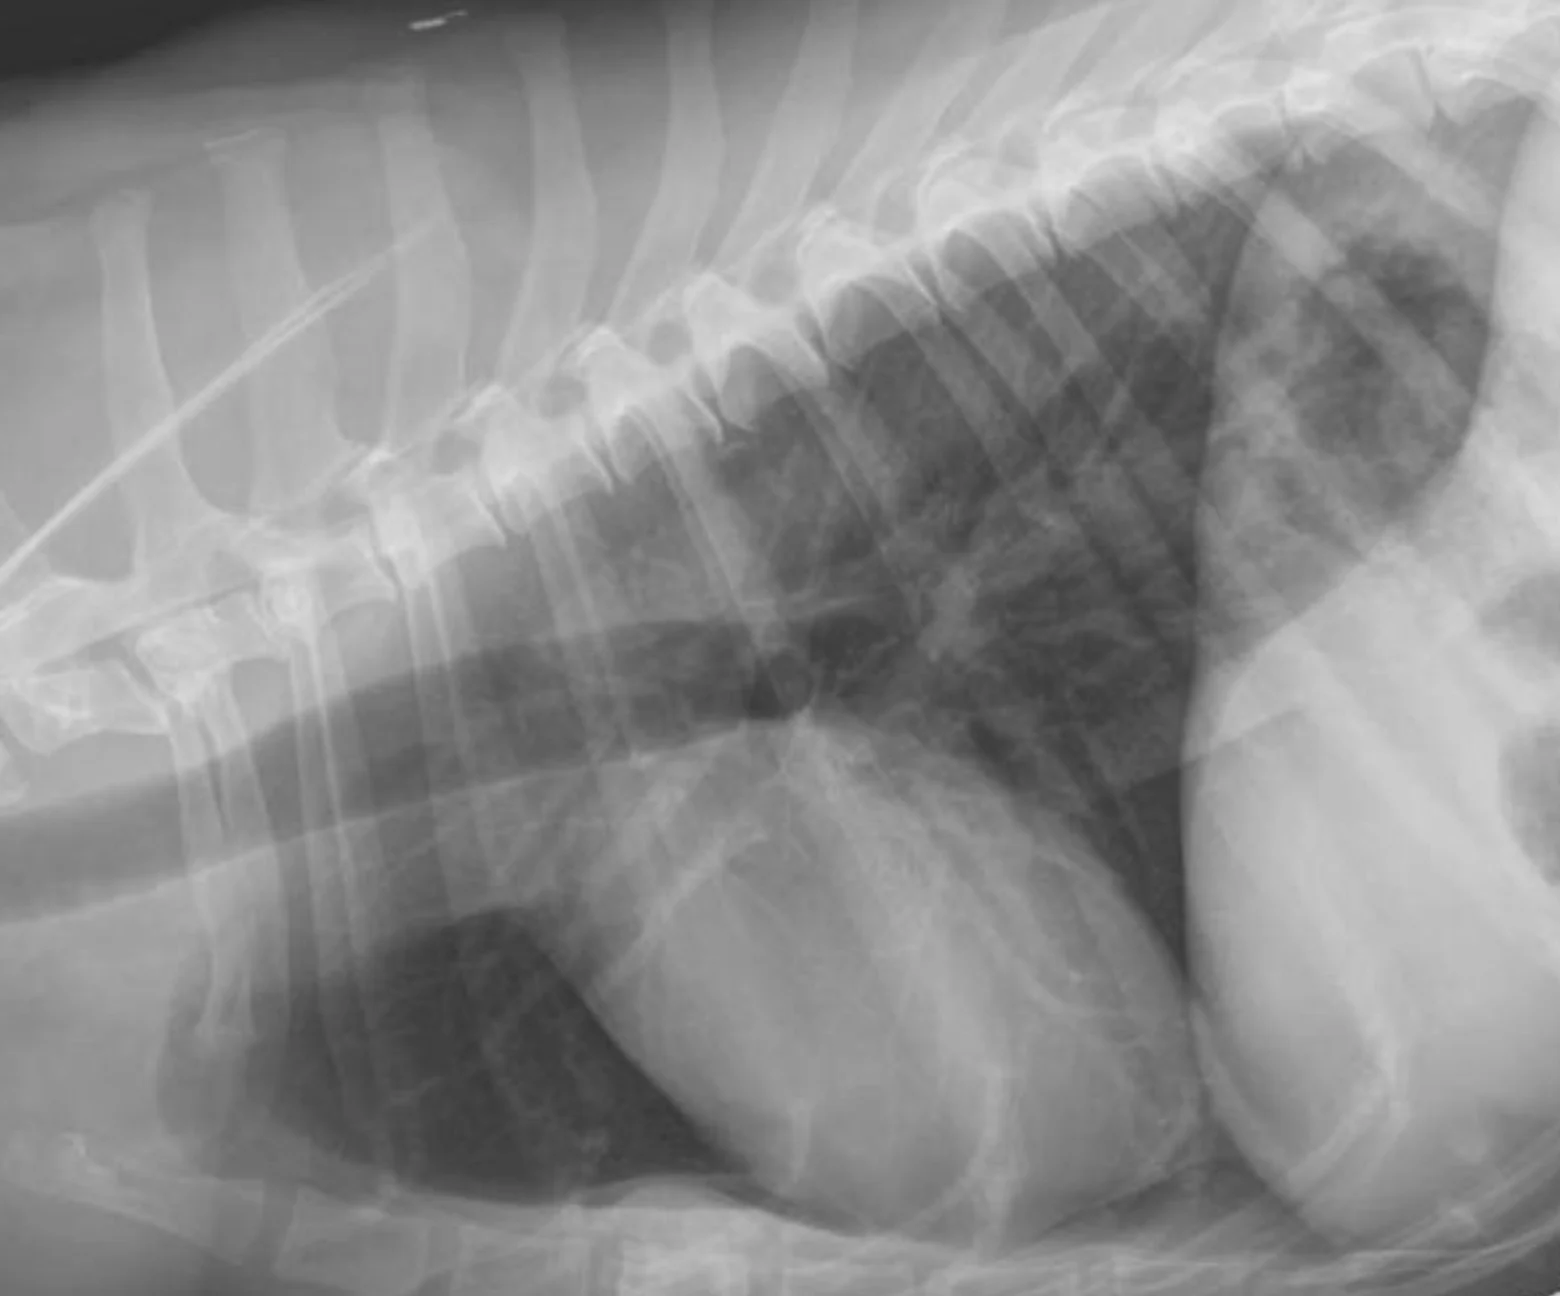

Remember to develop the films with fresh, clean developing solutions-old or exhausted developer will not work for developing technique charts. Examine the films for the setting that gives the best diagnostic quality. In Figure A, the kVp was 56, mA setting was 200, and time was 0.0125 seconds (mAs = 2.5). In this example, the bones are not easily visualized and the film overall is too white (underexposed).

In Figure B, the kVp and mA were left the same and the time was changed to 0.025 seconds (mAs = 5). In this image, the body wall, abdominal organs, and bones can all be readily visualized; this is a proper exposure. In Figure C, the kVp and mA were left the same and the time was changed to 0.05 seconds (mAs = 10). With this higher exposure technique, the ventral body wall cannot be visualized, and the abdomen is too dark (overexposed).